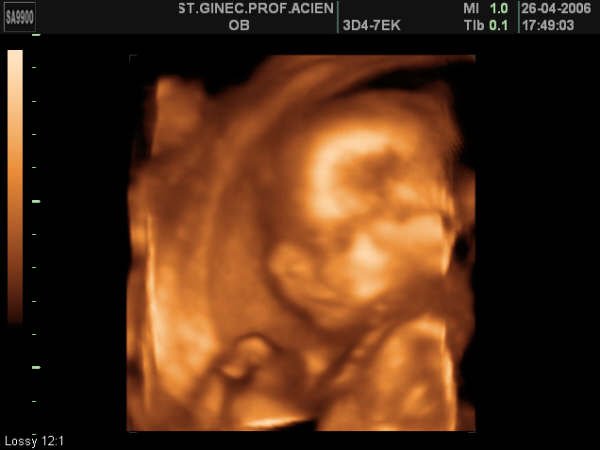

La cabecita superaba la media que "debía" tener....te haces una eco en 3d para ver si ahi te pueden asegurar algo del estado de tu hijo,y lo único que consigues con ella,es una fotografía de los mas bonita y viendose casi todos los rasgos de tu niño,para ponerla de fondo de escritorio y venir a llorar delante del pc cuando todos duermen y hablar con ella..pedirle que esté bien,que no le pase nada..y es mas..llegar a pedirle a esa pantalla de ordenador donde está la foto de tu hijo, que sea como sea,que esté como esté, no nos deje ahora sin él y llegue a este mundo.